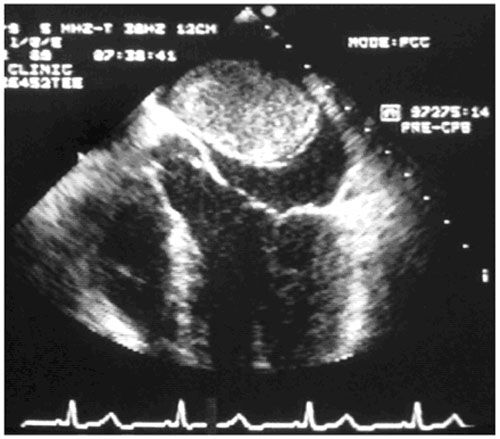

Диагностика опухоли сердца